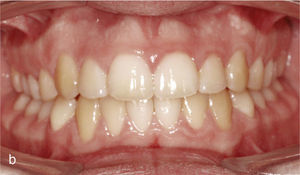

EspaciosEl cierre de espacios en el sector anterior se clasifica dentro de los movimientos dentales sencillos con el sistema Invisalign. En la vista intraoral de la figura 6a se observan sendos sectores anteriores con espacios en maxilar y mandíbula. Se realizó el cierre de los espacios y también la intrusión de los dientes 11 y 21. Con dicho fin fueron adheridos ataches rectangulares en los dientes 13, 23, 11 y 21. La imagen intraoral de la figura 6b muestra el resultado del tratamiento después de cerrar los espacios y de reducir la sobremordida vertical.

Vista intraoral de los dientes anteriores separados entre sí y de los ataches en los dientes 13, 11, 21 y 23 para el cierre de los espacios y también en los dientes inferiores 33, 34, 35, 43, 44 y 45 para obtener el anclaje necesario para la intrusión de los dientes anteroinferiores (a). Vista intraoral del resultado después del cierre de espacios y de la creación de una sobremordida horizontal y vertical fisiológica (b).